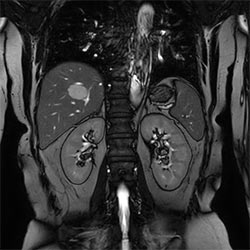

Pelvis